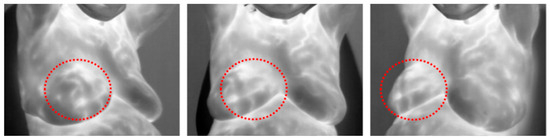

- DMR-IR Dataset: The Database for Mastology Research Infrared (DMR-IR) dataset [39] is the most widely used database in research studies. Of the 26 studies covered in this review, 20, 77%, used this dataset. The DMR-IR dataset includes infrared (IR) images, several digitized mammograms, several ROI masks, and clinical data for 293 patients captured at the Hospital Universitario Antonio Pedro (HUAP) of the Federal University Fluminense. The use of this dataset was approved by the Ethical Committee of the HUAP and registered with the Brazilian Ministry of Health under number CAAE: 01042812.0.0000.5243 and is publicly available at http://visual.ic.uff.br/dmi/, accessed on 6 April 2025. Infrared images are captured using Static Image Thermography (SIT) and Dynamic Image Thermography (DIT) described in [19]. The database also includes segmented images for 56 patients (37 sick and 19 normal). Figure 4 shows sample images from this dataset.